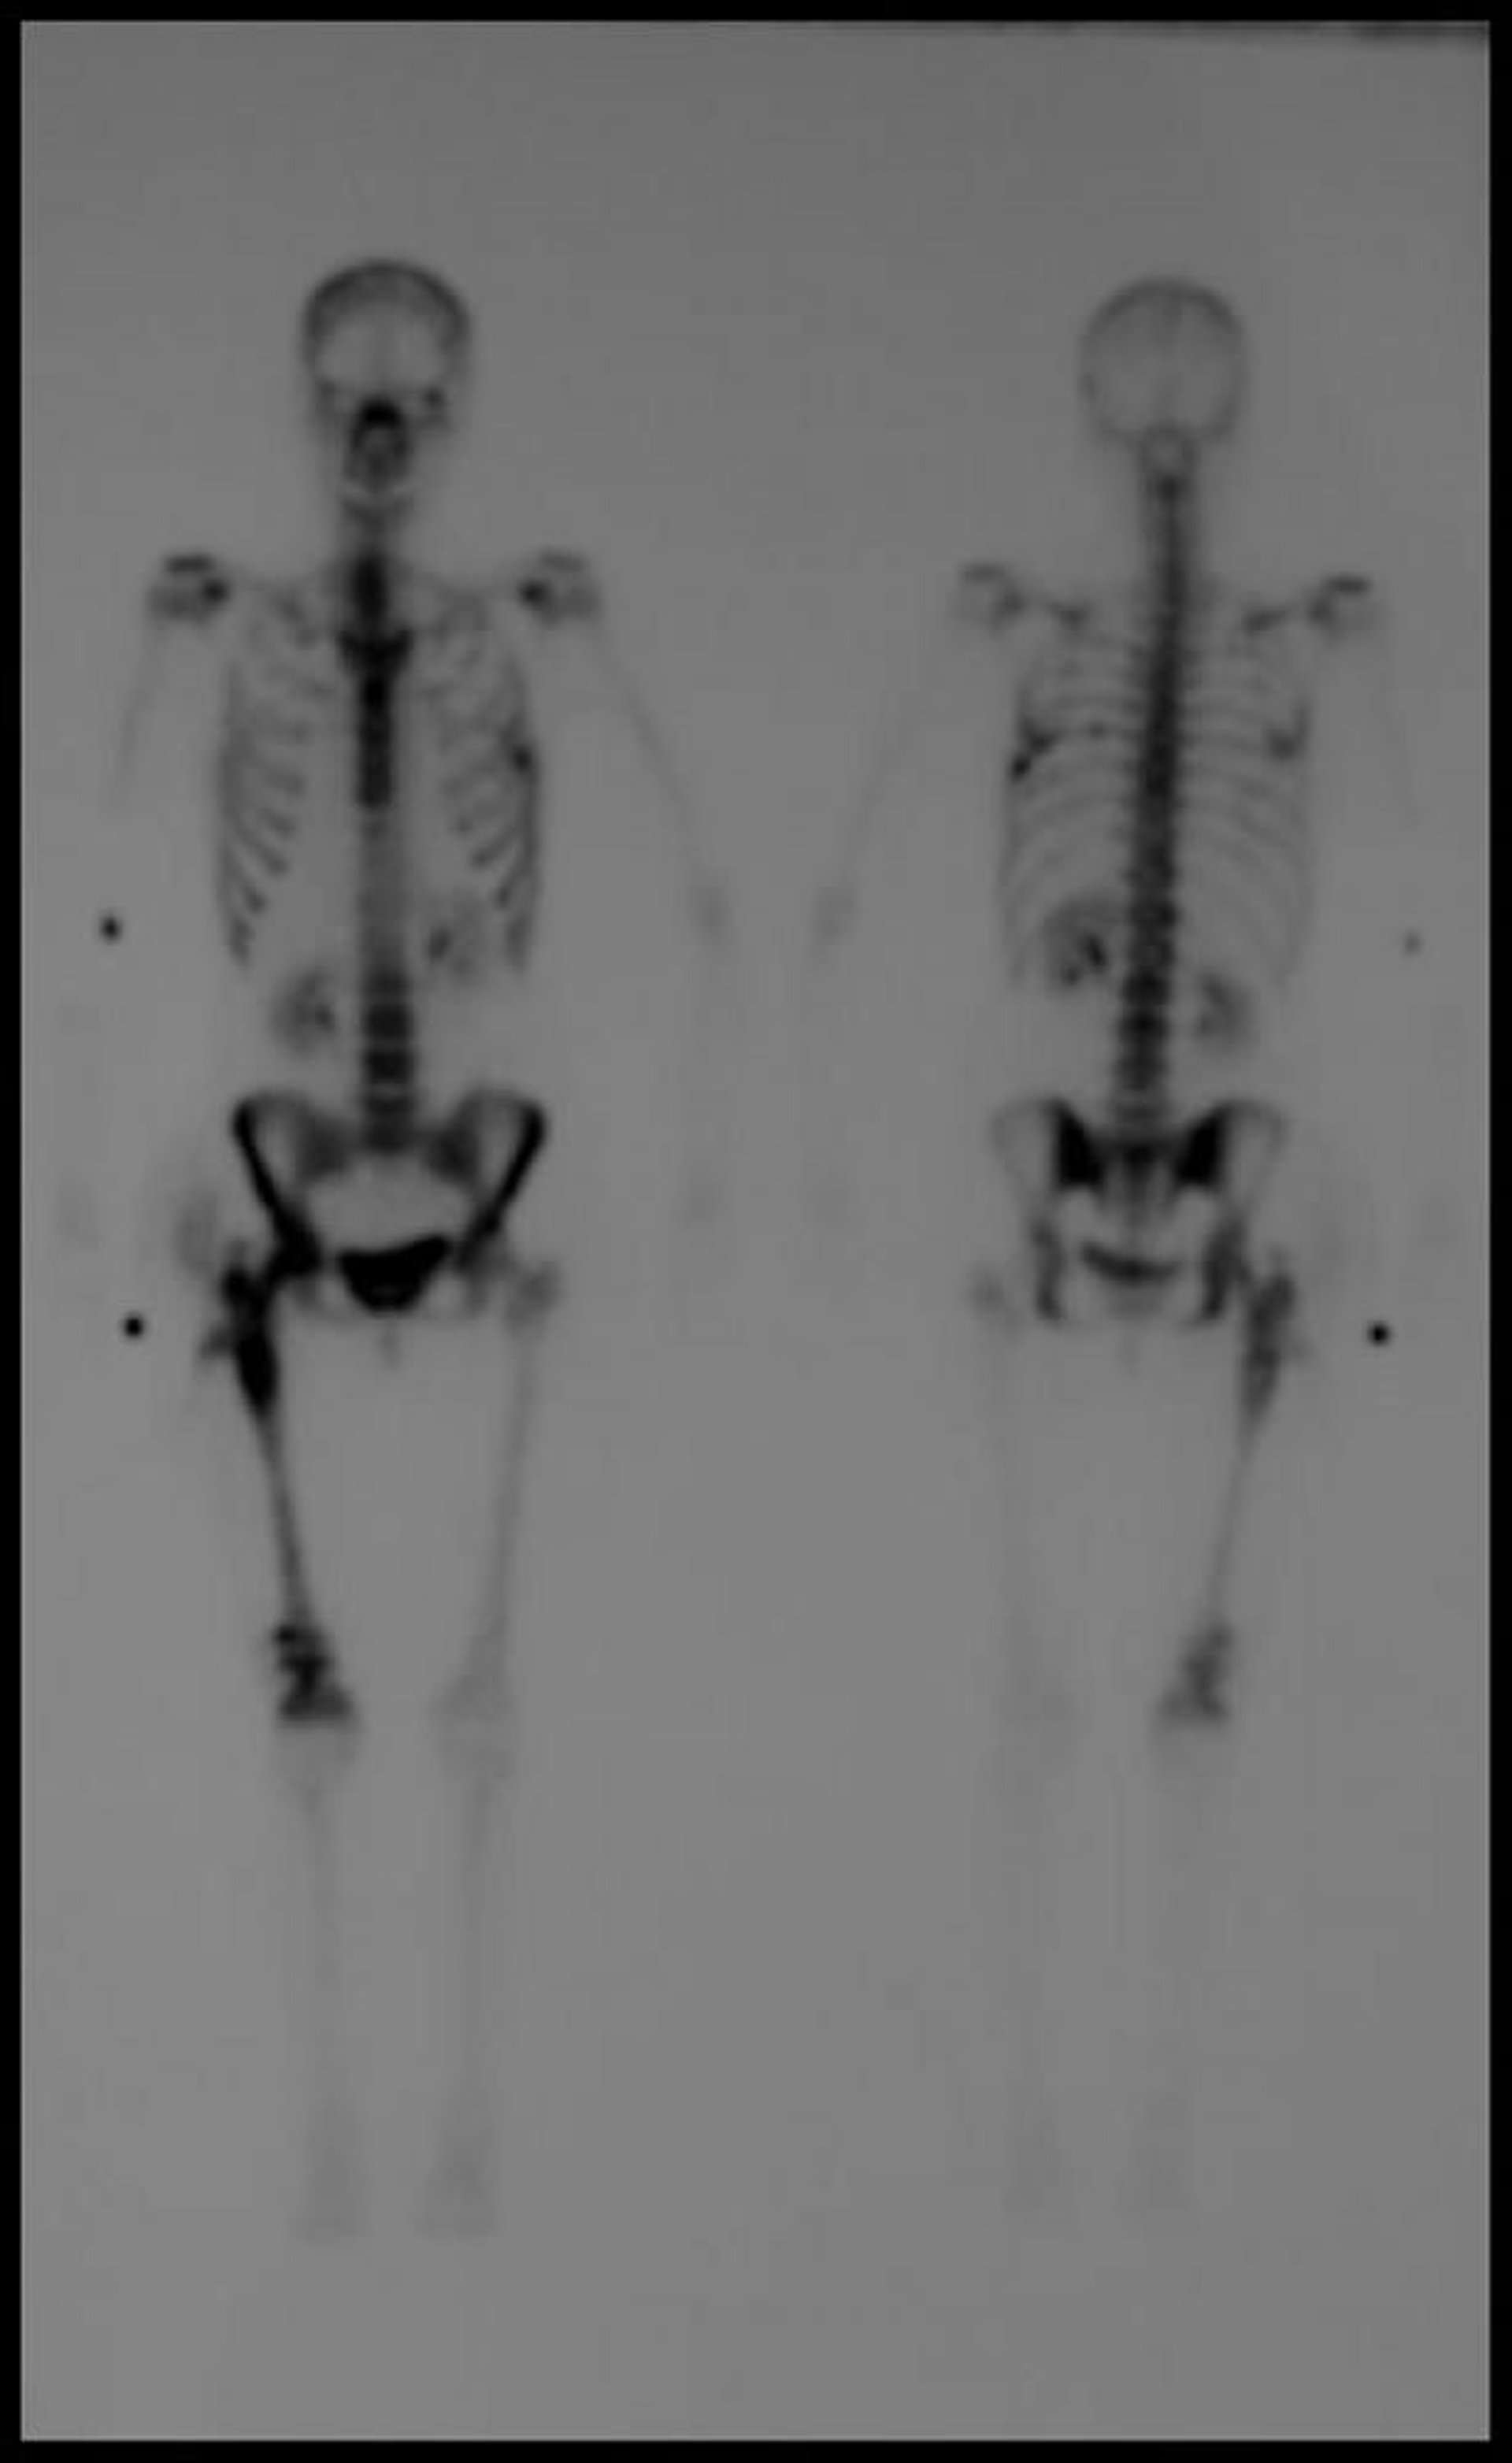

Остеосцинтиграфия всего тела

Изображение, выполненное с помощью отсроченной остеосцинтиграфии всего тела с технецием-99m, показывает множественные очаги повышенного поглощения, соответствующие картине метастатической болезни.

Image courtesy of Hakan Ilaslan, MD.